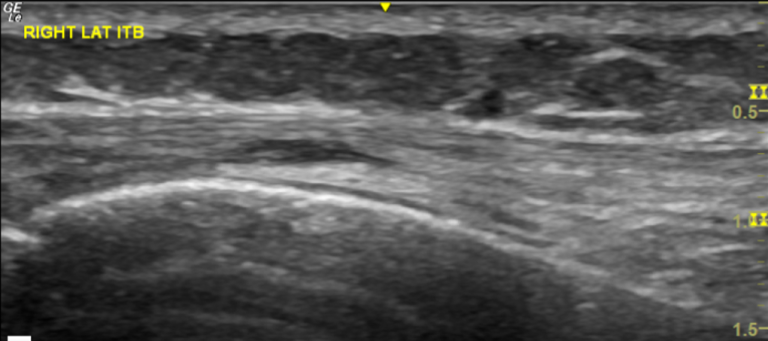

Diagnostic Ultrasound:

Diagnostic ultrasound is very helpful for assessment of iliotibial band friction syndrome. As this is a dynamic modality we we will be able to see the IT band as it moves over the lateral epicondyle of the knee during extension and flexion of the knee. This allows us to evaluate for any thickening of the ITB but also to identify any iliotibial bursitis which is indicated by fluid in the iliotibial bursa.

ruling out other potential sources of lateral knee pain such as ligamentous injuries or meniscal tears.

The ultrasound-guided injection procedure allows very specific targeting of the iliotibial bursa. The bursa is clearly identifiable on ultrasound and for a skilled practitioner the needle is then accurately guided in the ITB bursa which lies superficial of the lateral femoral condyle and underneath the iliotibial band. The accurate administration of steroid also avoids potential weakening of the IT band by inadvertent injection in the body of the IT band which is very realistic possibility if this injection is done unguided.